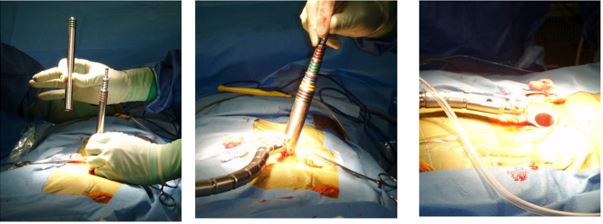

3.2. Chụp cộng hưởng từ (MRI).

Chụp cộng hưởng từ được coi là phương pháp chẩn đoán hình ảnh hiện đại, có độ tin cậy nhất trong chẩn đoán các bệnh lý thoát vị đĩa đệm. Trên các phim cộng hưởng từ có thể xác định chính xác vị trí, số tầng thoát vị, hình thái thoát vị (trung tâm, cạnh trung tâm và lỗ ghép).

Hình 2. Hình ảnh thoát vị đĩa đệm trên cộng hưởng từ